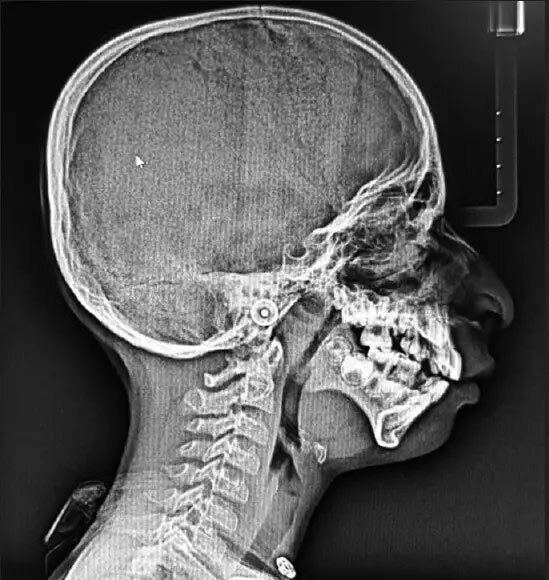

پس از یک سری معاینات، مشاوره و آزمایش ژنتیک، متخصصان پزشکی در نهایت به یک تشخیص قطعی رسیدند؛ سندرم تریچر کالینز (TCS). این اختلال ژنتیکی نادر بر رشد استخوانها و بافتهای صورت در طول رشد جنین تأثیر میگذارد و منجر به ناهنجاریهای صورت و اختلالات شنوایی میشود. اعتقاد بر این است که ناشی از جهش در ژنهای TCOF1، POLR1C یا POLR1D است، اگرچه در برخی موارد، علت ناشناخته باقی میماند.

سندرم تریچر-کالینز که به نام دیسوستوز فک پایین نیز شناخته می شود، یک اختلال ژنتیکی بسیار نادر است که تقریباً از هر 50000 تولد زنده 1 نفر را تحت تأثیر قرار می دهد. اگرچه شدت این بیماری در بین افراد متفاوت است، ویژگی های مشترک عبارتند از: TCS اساساً استخوانها و بافتهای صورت را تحت تأثیر قرار میدهد و در نتیجه استخوانهای گونه، فک و چانه رشد نکرده است. در نتیجه، افراد مبتلا اغلب ظاهری متمایز دارند که با چشمهای متمایل به پایین، گوشهای کوچک و بد شکل و چانه عقبرفته مشخص میشود.

علاوه بر ناهنجاری های صورت، TCS می تواند منجر به از دست دادن شنوایی به دلیل ناهنجاری ساختارهای گوش میانی شود. کم شنوایی در میان افراد مبتلا به TCS رایج است و نیاز به مداخلاتی مانند سمعک یا جراحی های اصلاحی دارد.

ساختارهای فک و صورت توسعه نیافته می تواند راه هوایی را مسدود کند و منجر به مشکلات تنفسی، به ویژه در هنگام خواب شود. علاوه بر این، نوزادان مبتلا به TCS ممکن است در تغذیه با مشکلاتی مواجه شوند که نیاز به مراقبت های تخصصی و تکنیک های تغذیه ای دارد.